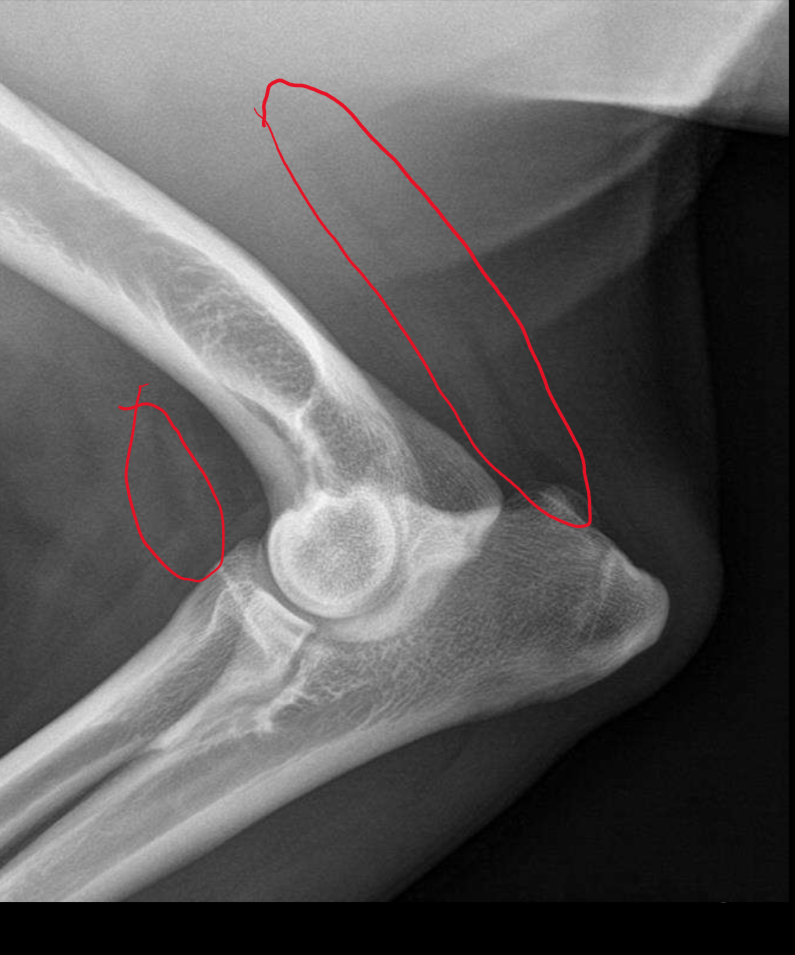

Fascial plane. Cranial is infrapatellar fat pad. Caudal fascial plane

Fascial planes

Which is abnormal and why?

Right because infrapatellar fat pad is indented and caudal fascial plane is obstructed